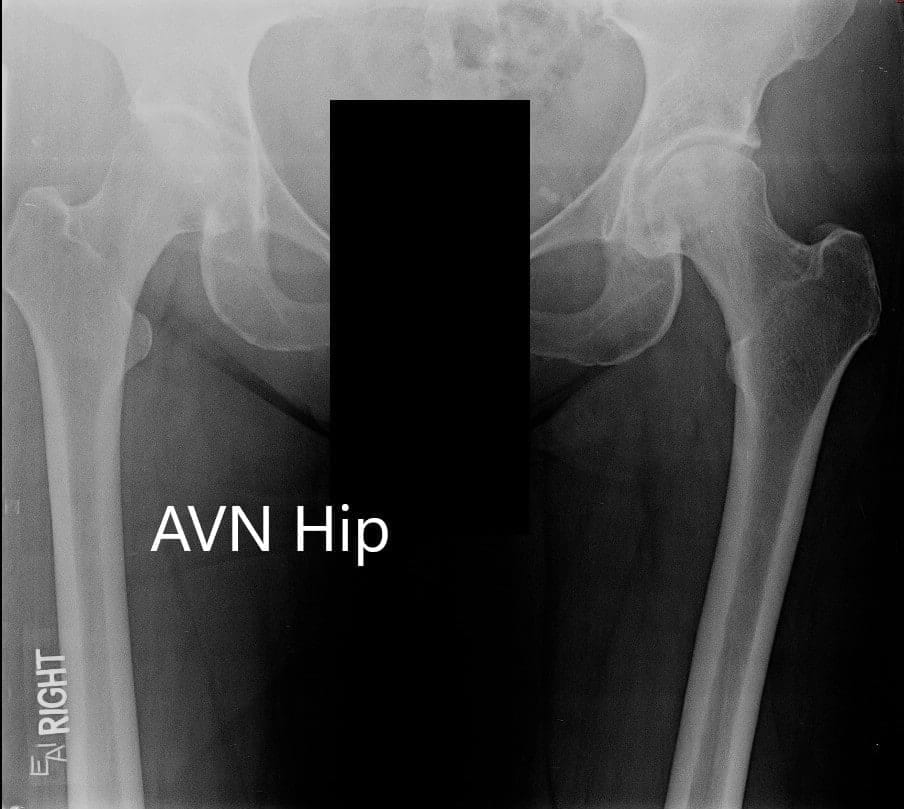

Las imágenes revelaron cambios osteoartríticos en la cadera izquierda con una lesión de la RNV que afecta al 60% de la cabeza femoral. Se realizó una resonancia magnética que reveló necrosis avascular femoral izquierda sin colapso subcondral evidente.

Radiografía que muestra la vista AP de la pelvis con ambas articulaciones de la cadera

Radiografía que muestra las vistas AP y laterales de pata rana de la articulación de la cadera izquierda